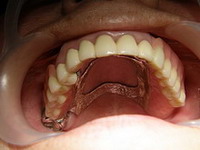

Situatie initiala

Punte din metalo-ceramica